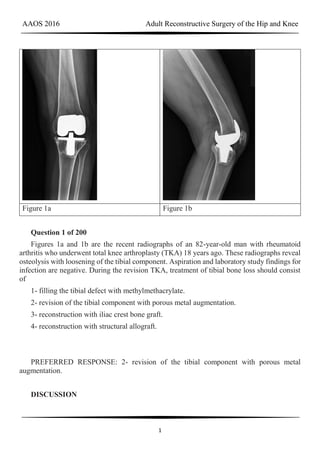

Figure 1a Figure 1b

Question 1 of 200

Figures 1a and 1b are the recent radiographs of an 82-year-old man with rheumatoid

arthritis who underwent total knee arthroplasty (TKA) 18 years ago. These radiographs reveal

osteolysis with loosening of the tibial component. Aspiration and laboratory study findings for

infection are negative. During the revision TKA, treatment of tibial bone loss should consist

of

1- filling the tibial defect with methylmethacrylate.

2- revision of the tibial component with porous metal augmentation.

3- reconstruction with iliac crest bone graft.

4- reconstruction with structural allograft.

PREFERRED RESPONSE: 2- revision of the tibial component with porous metal

augmentation.

For severe tibial defects (Anderson Orthopaedic Research Institute [AORI] types 2 and 3),

metaphyseal fixation is necessary to achieve construct fixation during revision TKA.

Metaphyseal fixation may be achieved with cement, structural allograft, or conical metallic

implants. The major concerns regarding structural allograft are graft resorption and mechanical

failure and technical issues related to fashioning the graft and obtaining a good host-allograft

interface. In a systematic review, porous metal cones were associated with a decreased

loosening rate in AORI 2 and 3 defects compared to structural allografts. Metallic trabecular

metal cones and metaphyseal porous coated sleeves provide a stable construct with which to

support the tibial component during revision TKA. Clinical results with these devices include

good metaphyseal fixation for severe tibial bone defects.